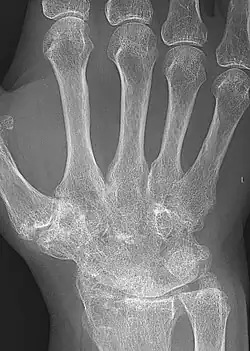

X-rays of the hands and feet are generally performed when many joints are affected. In RA, there may be no changes in the early stages of the disease, or the X-ray may show osteopenia near the joint, soft tissue swelling, and a smaller than normal joint space. As the disease advances, there may be bony erosions and subluxation. Other medical imaging techniques such as magnetic resonance imaging (MRI) and ultrasound are also used in RA.[20][79]